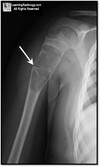

What pathology is present?

Monteggia # | One bone fractured, other bone dislocated